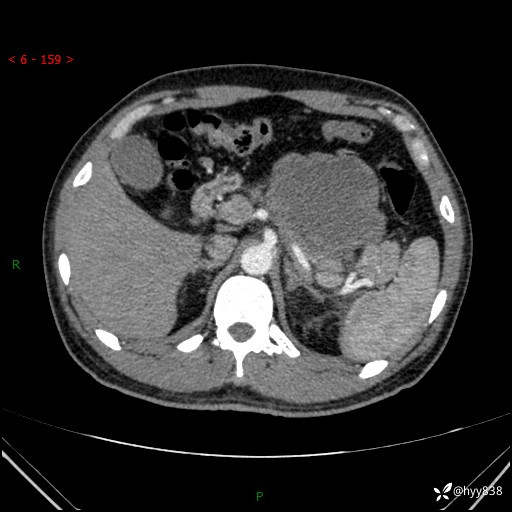

病例39岁/女,左侧腰痛入院。腹腔囊实性肿块,定位、定性---结果公布~

性别:男

年龄:39岁

简要病史:左侧腰痛待查,CT发现腹腔占位

腹部CT平扫+增强